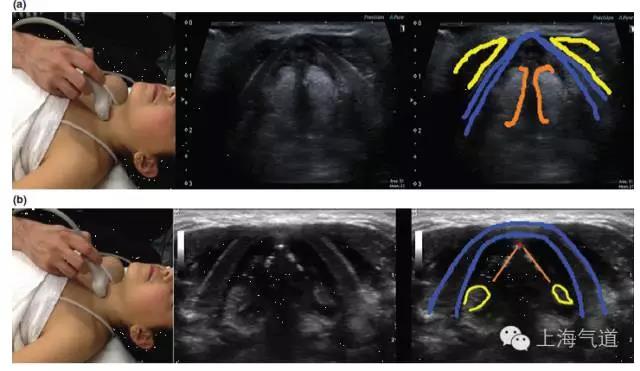

图4a. 假声带水平横截面显示,黄色为带状肌,蓝色为甲状软骨,橙色为假声带。b.将探头轻微向尾端移动至真声带水平,蓝色为甲状软骨,橙色为真声带,红色为前联合,黄色为杓状软骨